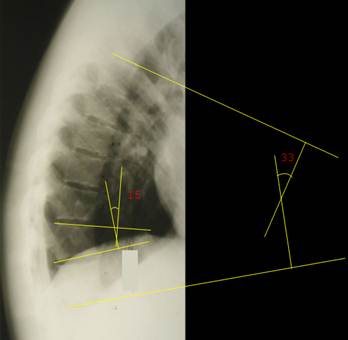

Слева

изображена боковая рентгенограмма

грудного отдела позвоночника ребенка 16 лет с компрессионным переломом 9 и 10

грудных позвонков, уже вами виденная. По методу Кобба выполнено определение

угла клиновидной деформации 10 грудного позвонка (15°), а также угла крудного кифоза (33°). Справа

изображена боковая рентгенограмма грудного отдела позвоночника ребенка 9 лет,

тела грудных позвонков имеют физиологическую клиновидность, что затрудняет

определение угла грудного кифоза по методу Кобба. Выполнено определение угла

грудного кифоза по методу Фергюсона (25°) – просто, изящно,

удобно.